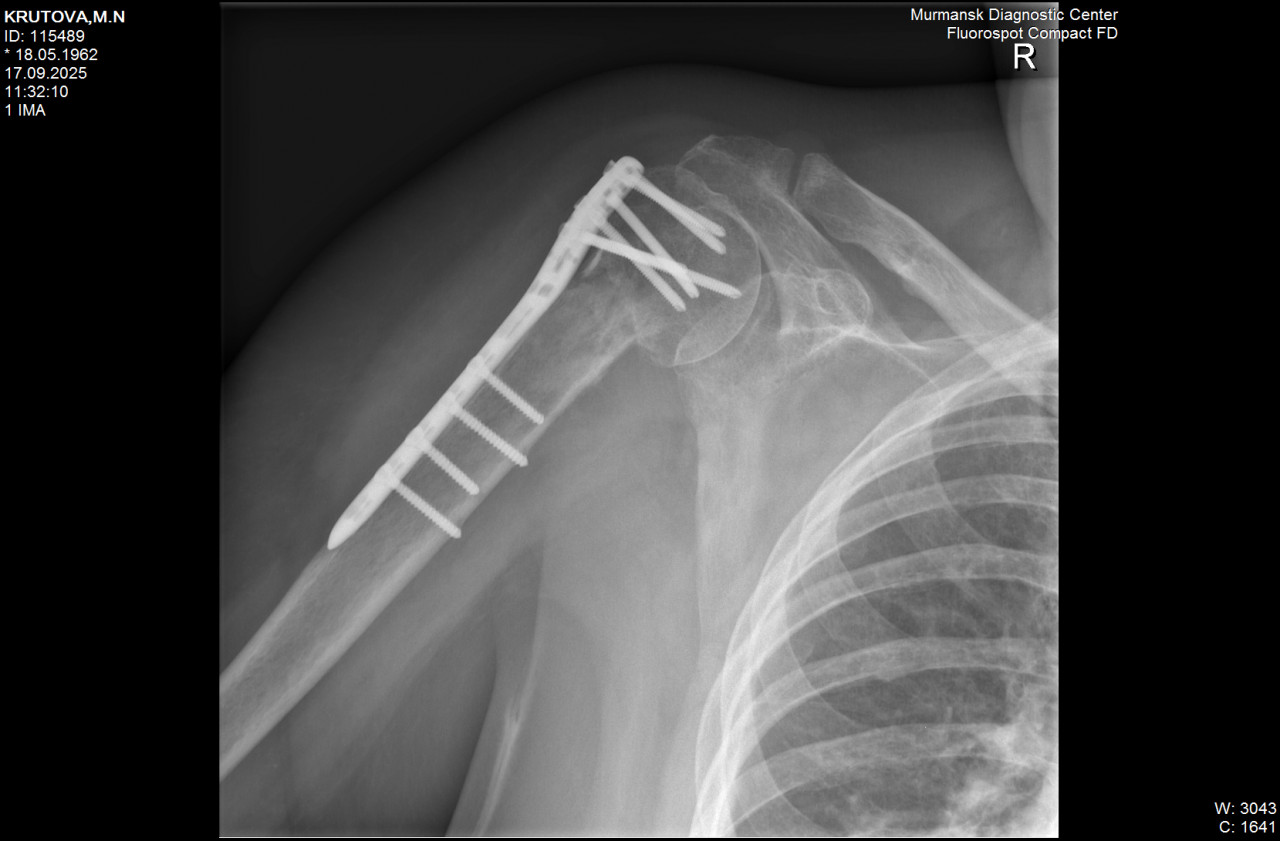

Здравствуйте! в июне перелом плеча и отрыв  большого бугорка. В июле ГИОХВ правого плечевого сустава. Сейчас в суставе бывают болевые ощущения. Рентген от 17.09.25. Насколько верно описание (делал молодой лаборант)

Здравствуйте. По рентгену видно наличие металлоконструкции, сохранность пластины и винтов, однако признаков полноценного сращения перелома пока нет, отмечается зона резорбции костной ткани, что может указывать на замедленное заживление и риск формирования ложного сустава. При диабете такие осложнения встречаются чаще, поэтому обязательно нужно очно показаться травматологу для уточнения тактики.

Здравствуйте.  По снимкам металлоконструкция стоит правильно, перелом фиксирован, но видны признаки замедленного срастания и участок перестройки костной ткани. Это может быть вариантом замедленной консолидации, не всегда остеомиелит. Важно наблюдение в динамике и дообследование (анализы, КТ/МРТ при необходимости), решение о дальнейшем лечении принимает травматолог очно.